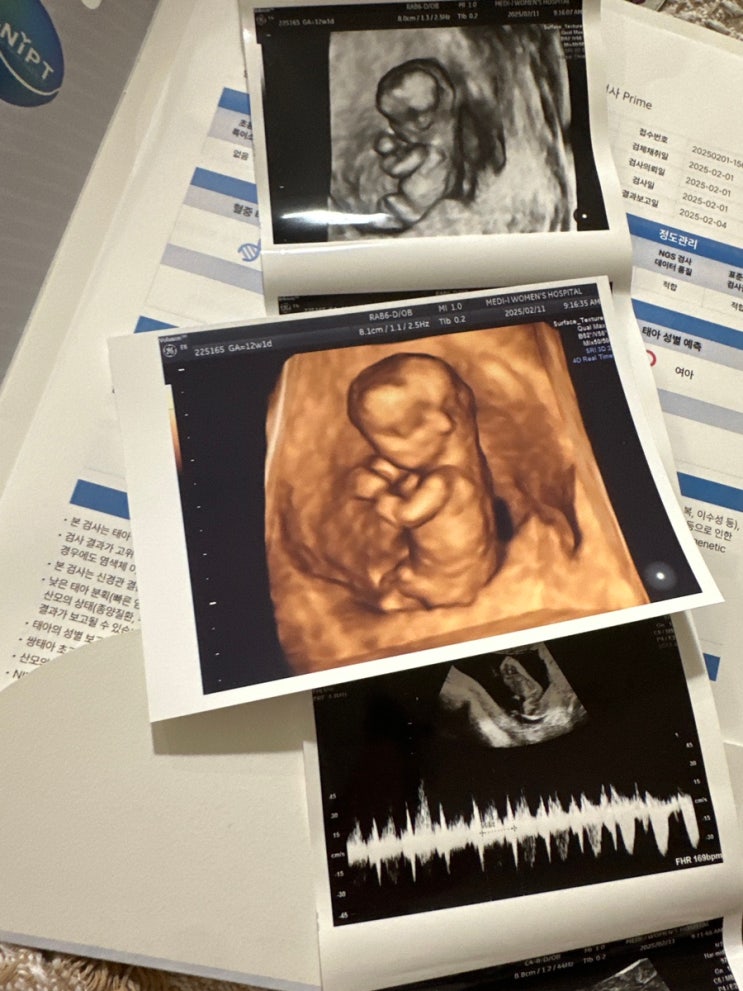

노원 메디아이 임신 10주차 니프티 검사 후기 녹십자GNIPT 12주차 정밀초음파

니프티검사 후기 의사선생님이 8주차에도 정상이다 니프티..굳이?라고 하셨지만 빨리 안심하고 싶어서 거금...

임신 8주차 초음파 젤리곰 천사링 8주차심장박동수

임신8주차 초음파 6주에 심장 박동수 120bpm듣고 어벙벙했던,,, 2주동안 꾹 참고 출산하게될 병원으로 예약...